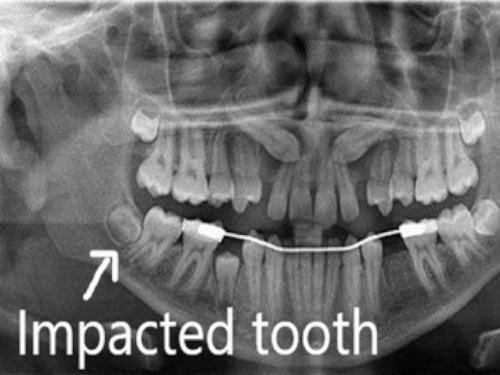

Being the last tooth in our jaw they often do not have any space to erupt in the oral cavity and are therefore found or discovered hidden or impacted usually on an Xray

They may therefore be positioned differently and have to be examined by an OPG Xray

OPG showing 3 different 3rd molars oriented differently

OPG showing all the 4 wisdom teeth and their positions

The impacted that is not fully erupted third molars have to be extracted surgically. Under local anesthesia the bone and the soft tissue that is hindering its eruption are removed and then extraction is carried out followed by sutures